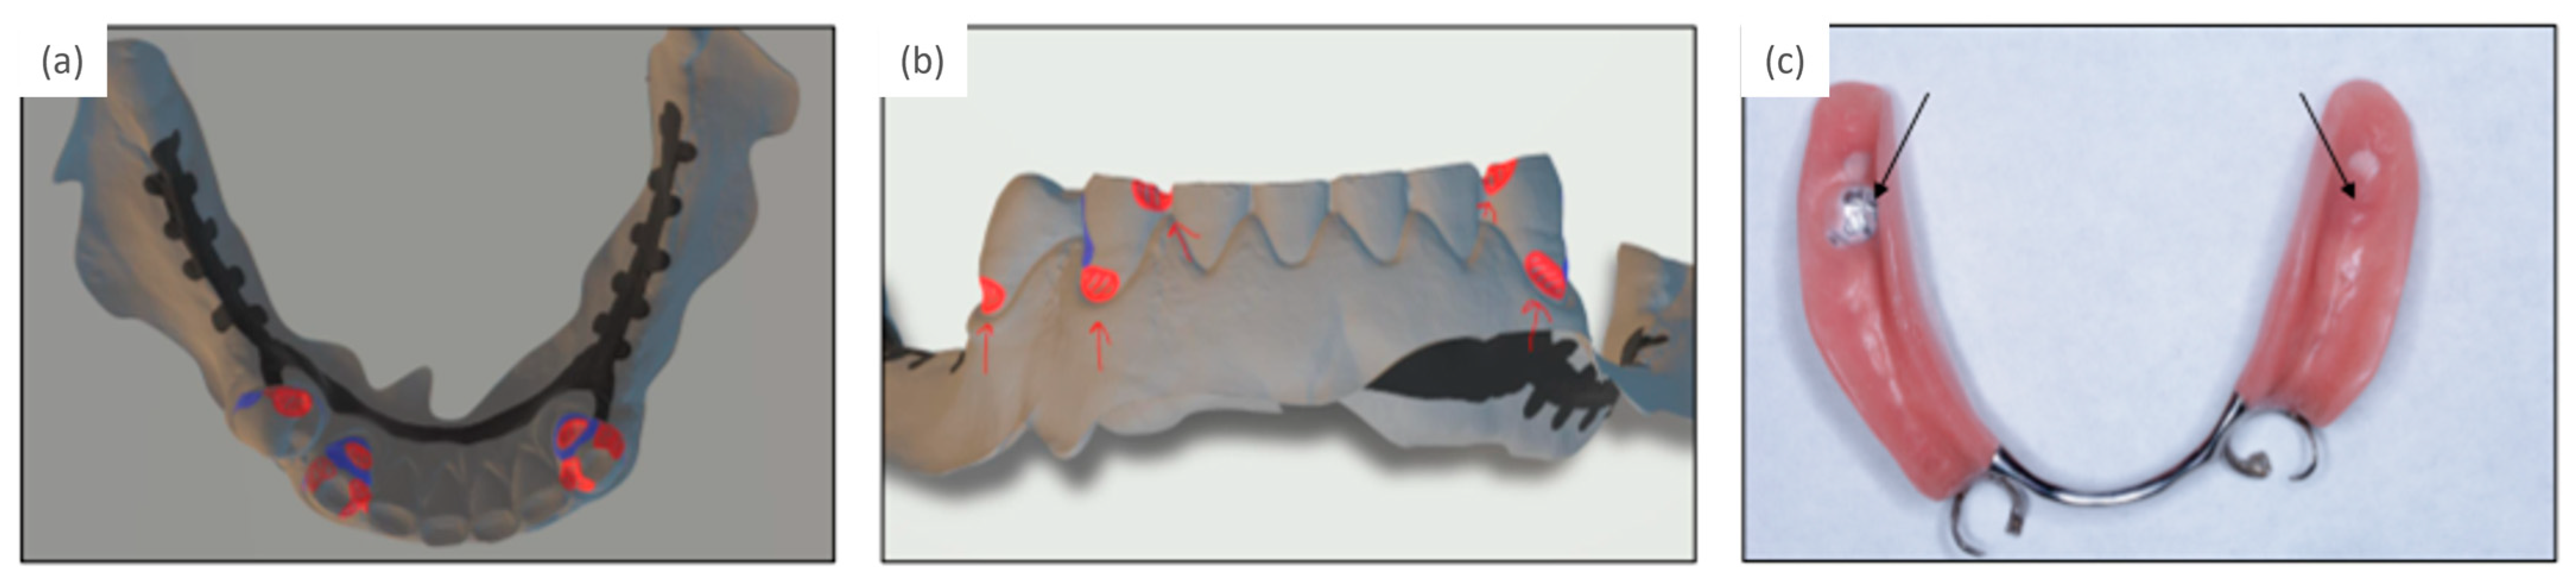

Due to the complex intermaxillary situation requiring an increase in the vertical dimension of occlusion (VDO), an overdenture prosthesis with anterior post copings and a clasp at the intact left premolar was planned in the maxilla, while a clasp-retained RPD was indicated in the mandible. The intact anterior dentition in the mandible determined the occlusal plane, and the increase in VDO was planned in the maxilla, which was restored first providing a diagnostic set-up in the mandible. For the RDP in the mandible, intraoral scans with and without the set-up were analyzed with a software program (3Shape Dental Manager, Copenhagen, Denmark), which enabled an exact planning of the prosthesis path of insertion and the position of the retentive clasp undercuts at the abutment teeth. This digital analysis replaced the traditional way with mounting casts in a surveyor to determine the path of insertion and undercuts at the abutment teeth (Figure 2a,b). Required occlusal rest cavities were prepared and a new intraoral scan was taken, which in turn was incorporated into the further planning. The RPD was then designed in the planning software and configured with 2 clasps at the most distal abutment teeth and an extension of the bilateral saddles to ensure support on the retromolar pads. In addition, the housings in the metal framework were scheduled for later implant healing abutments or retention elements in the area of the second molars (Figure 2c).

Implant placement was performed fully guided with the printed surgical guide (Figure 4a). Two ultra-short tissue-level implants with a diameter of 4.1 mm and 4 mm intraosseous length (Straumann AG, Basel) were inserted in the posterior molar region (Figure 4b) and left for submerged healing; in the case of an existing interims prosthesis, the saddles have to be relieved in the wound area (Figure 4c).

When the fully navigated implant placement corresponded to the virtual implant planning, the virtually planned prosthesis was fabricated using a chromium-cobalt restoration by a milling process in a high precision milling machine (PFM 4024-5D, Primacon, Peissenberg, Germany) completed with denture teeth and the prostheses saddle. The RPD was incorporated after completion of wound healing approximately 3 weeks after surgery. In the event of significant manual corrections of the implant position, a new intraoral scan or an analog impression has to be taken to visualize the approximate implant position. The virtual RPD planning can be adjusted accordingly, and the prosthesis fabricated.

Following a 3-month submerged implant healing period, abutment connection was conducted, and retention elements were inserted (Novaloc, Straumann; Figure 4d–g). The height of the elements were selected taking into account the height of the mucosal peri-implant tissues and the vertical space (Figure 4d). Matrices were fixed in the RPD using self-curing methylmethacrylate resin (Unifast Trad, GC Europe AG, Luzern, Switzerland) (Figure 4f). The patient’s perception of the RPD before and after connection to the implant was assessed with questionnaires on function, stability, and satisfaction [18]; the OHIP-G14 and masticatory performance with a color mixing ability test [19]. Based on these, the patient indicated a beneficial impact on his perception and function after prosthetic rehabilitation with implant retention. Figure 5 shows the patient’s completed prosthetic restoration in both jaws (Figure 5) and Figure 6 provides an overview of the patient’s clinical treatment schedule (Figure 6).

Figure 2. (a,b) Planning tooth preparations for three clasp retentions, of which only the two most distal abutment teeth were restored with clasps, (c) final removable partial denture with housings for future implant retention or support (arrows).